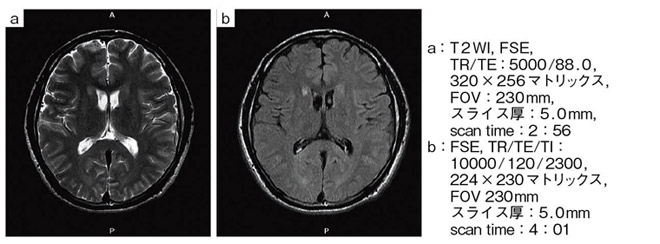

【RAPID Headコイルによる片麻痺症例】

【RAPID Headコイルによる片麻痺症例の頭部MRA】